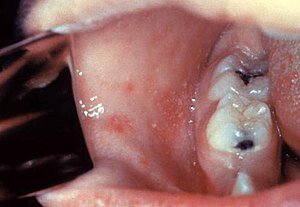

وی به برخی از علائمهای این بیماری اشاره کرد و افزود: از علائم سرخک میتوان به حالت سرماخوردگی، عطسه، سرفه و آبریزش بینی اشاره کرد. بعد از پیدایش این علائم، ضایعات پوستی از صورت شروع به نمایان شدن میکنند و در این حین ممکن است چشم به رنگ قرمز یا صورتی تغییر رنگ پیدا کند. یکی دیگر از نشانههایی که به پزشک معالج برای تشخیص این بیماری کمک شایانی میکند، لکههای سفید داخل دهان فرد است.